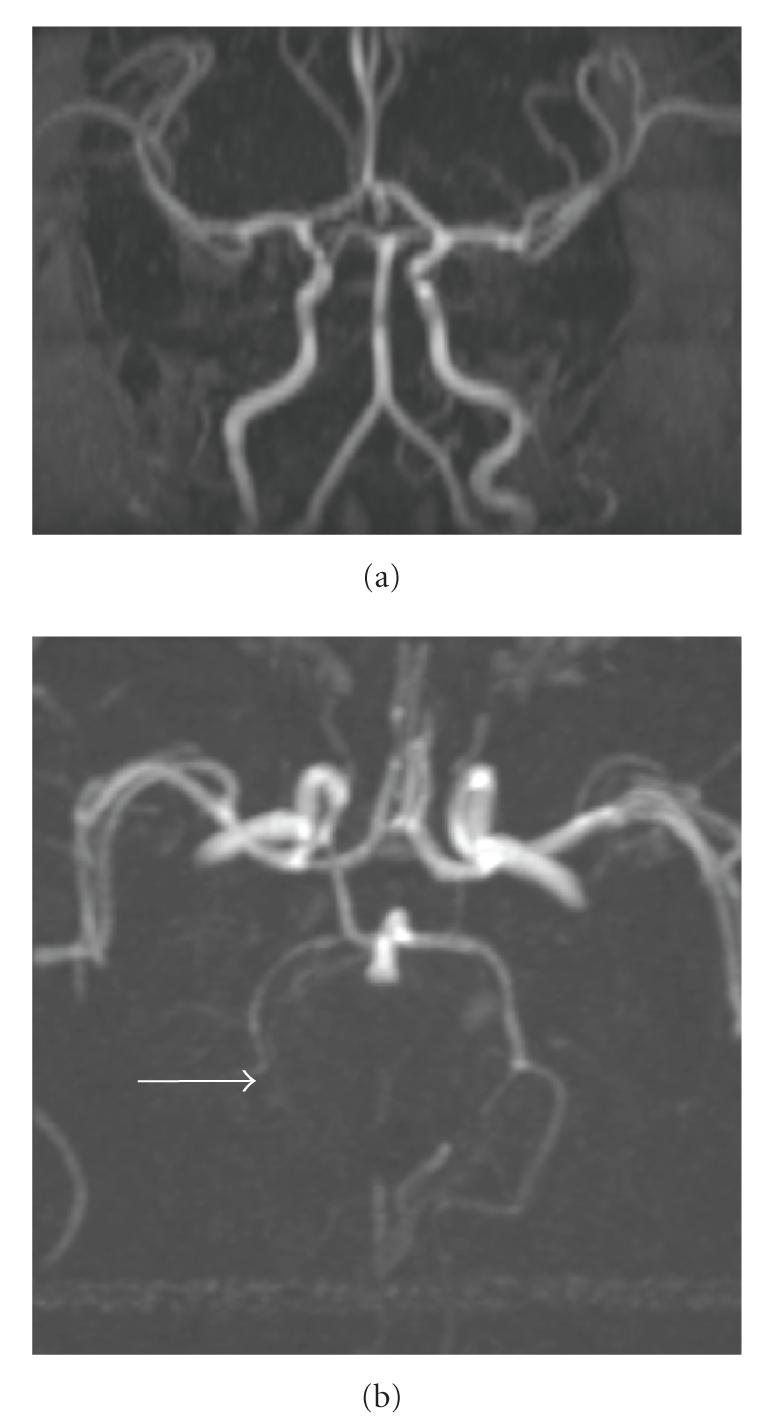

A full-term neonate suffered multifocal cerebral infarctions due to multiple large vessel thrombi. Thrombophilia and cardiovascular assessments were negative, but due to the severity of the lesions and the concern for expansion of the thrombi or future embolic events, treatment with low-molecular-weight heparin (LMWH) was initiated. No complications from treatment were experienced. We present this severe case in order to highlight difficult management decisions for newborns with multifocal perinatal thromboembolic stroke and to stress the need for further practice guidelines and research in this area.